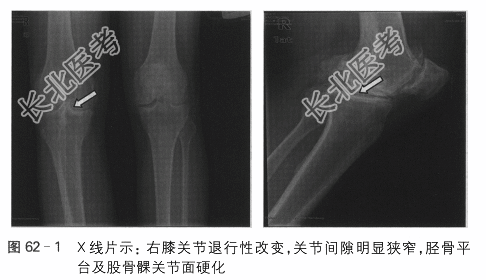

右膝关节X线片:右全膝关节置换术后改变,如图62-2所示。